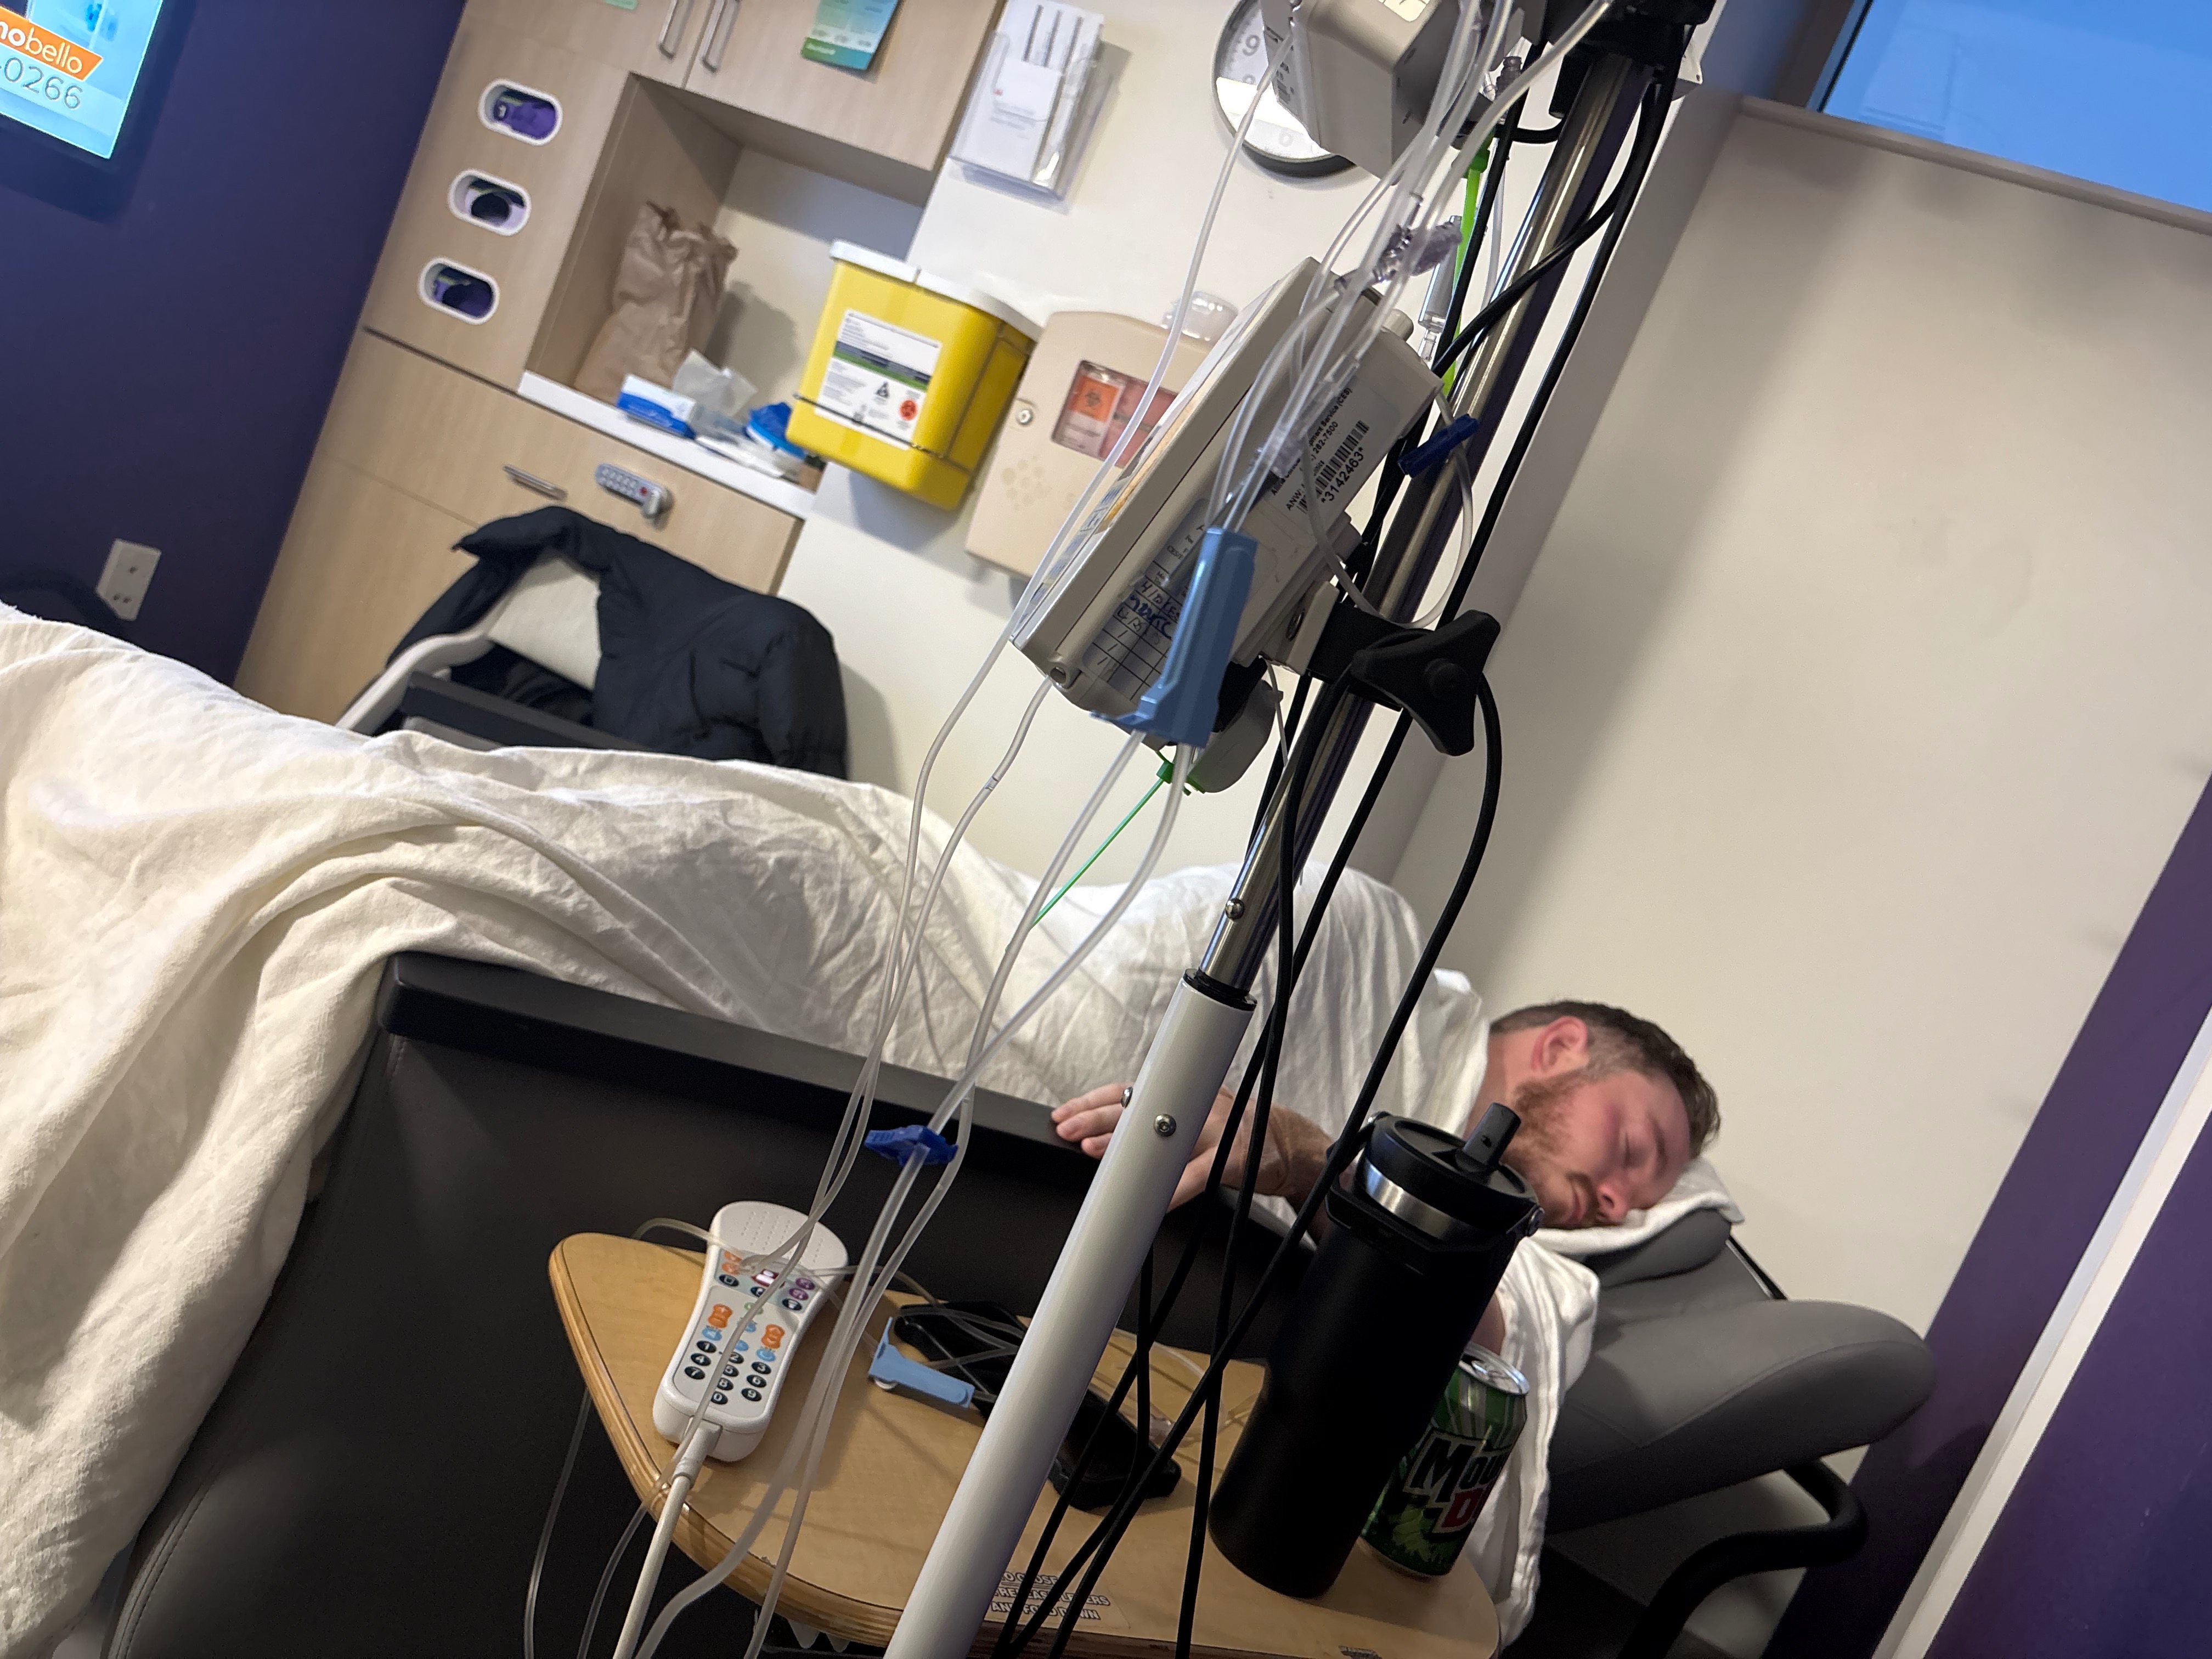

My son Brock was recently diagnosed with a very rare form of lung cancer. He’s only 28 and has never been a smoker, so as you can imagine, this news has come as a huge shock to him, and our entire family. Brock is currently receiving care in Minneapolis and will also be traveling to MD Anderson in March to ensure he gets the best possible treatment and outcome.